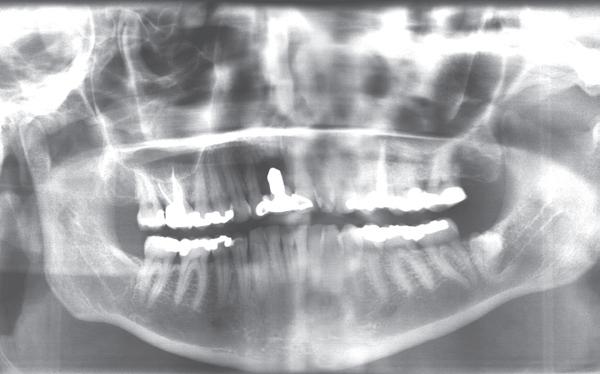

De diagnose luidde lokaal parodontitis met ernstige furcatie aandoeningen; Stadium IV (vergevorderd); graad C (snel progressief) (afbeelding 7) De elementen die niet te behouden waren, werden geëxtraheerd.

5. OPT intake

6. OPT na infectie controle

10. OPT-implantaten

9). In de bovenkaak werd bilateraal een sinuslift uitgevoerd. Aansluitend werden in beide kaakhelften implantaten geplaatst (afbeelding 10).